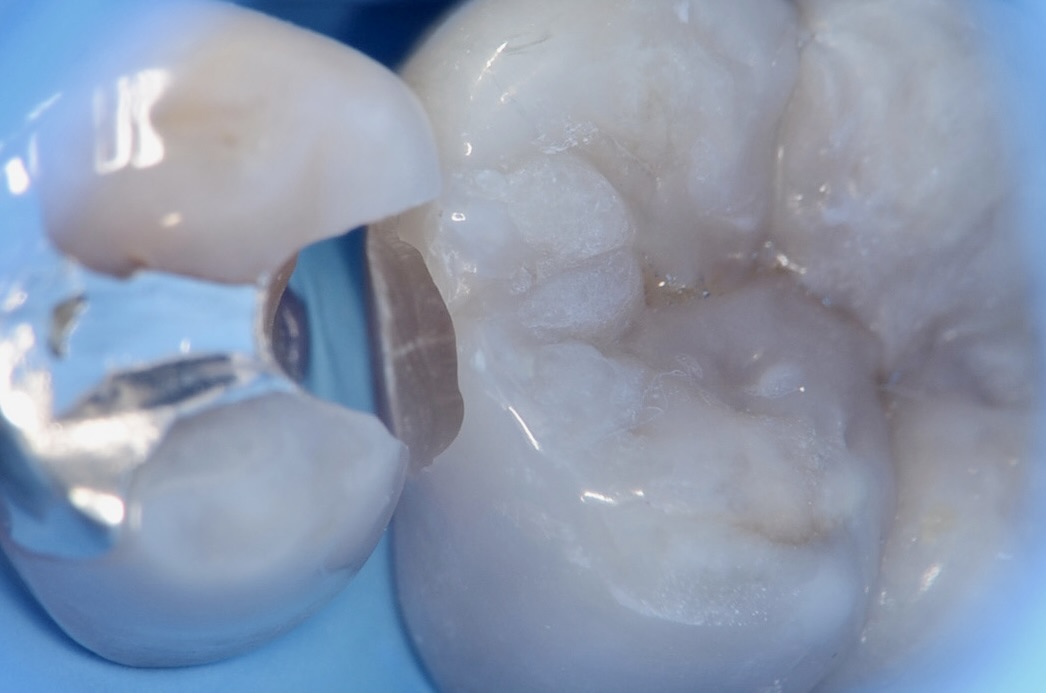

6番近心ダイレクトボンディング

フロワブルレジンの表面張力を活かし滑らかに充填します。 -